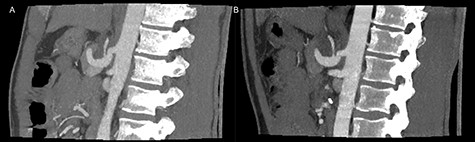

On admittance the patient had a pulse of 113 BPM, blood pressure of 125/60 mmHg and were anemic with a hemoglobin of 4.7 mmol/L. The patient underwent emergency contrast enhanced CT of both abdomen and cerebrum in venous phase without any pathological findings. Initial upper gastrointestinal endoscopy revealed a pulsating duodenal hemorrhage which could not be controlled endoscopically, and a laparotomy with duodenotomy and surgical hemostasis of a pulsating mucosal artery was performed. No classic duodenal ulceration was seen during neither gastroscopy nor duodenotomy. The patient was discharged 3 days later, but readmitted 6 days postoperatively due hematemesis and syncope. An emergency CTA showed stenosis and post-stenotic dilatation of CA and an aneurysm on a jejunal branch artery. The patient was circulatory stable and transferred to a tertiary center and underwent successful coiling of the gastroduodenal artery, gastroepiploic artery and two pancreaticoduodenal arterial branches. One month later a CTA, following a dedicated MALS protocol, visualized hook deformation of CA during expiration, significant stenosis and post-stenotic dilatation of CA (Fig. 1), all considered pathognomonic for MALS. An additional pseudoanurysm on the pancreaticodorsal artery was identified. The MALS angiographic protocol was performed using contrast-enhanced (100 ml Omnipaque 350 mg/ml, 3 ml/s) arterial scans in a maximum inspiratory phase followed by a maximum expiratory phase was performed with a 5 s delay between the respiratory phases.

Preoperative inspiratory (A) and expiratory (B) computed tomography scan, visualizing hook formation and stenosis of the celiac artery.